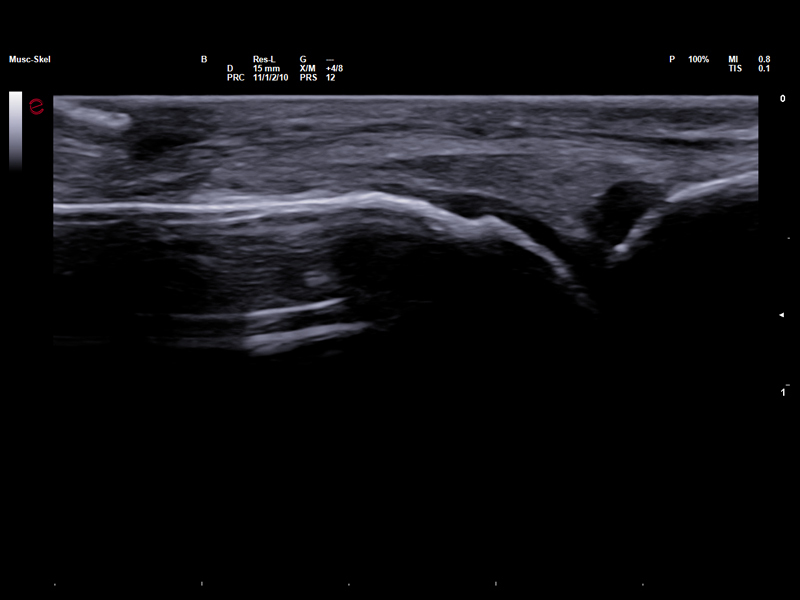

High-Frequency imaging for sport injury detection

Thanks to the advanced image quality of Esaote’s high-frequency probes, which operate at frequencies of up to 25 MHz, even micro-lesions can be clearly and precisely identified before they evolve into more serious injuries, thus empowering clinicians to stay one step ahead in injury prevention and management. The Very-High Frequency hockey stick probe, IHX 6-25, combines outstanding spatial resolution with advanced ergonomic design to facilitate needle access and perform accurate interventional gestures with millimetric precision.